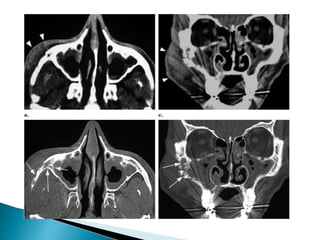

 Most patients with IFS do not have bone

erosion or extension of the disease outside of

the sinuses early in their course when salvage

is most likely. Recent data suggest

that unilateral thickening of nasal mucosa is

the most common initial finding on CT and

rhinoscopy in early disease .

 Unlike chronic invasive fungal sinusitis, acute

infection generally does not demonstrate hyperdense

material within the sinus on non-contrast CT. CT is

particularly effective at assessing bony changes.

Findings include 2:

◦ mucosal thickening: hypoattenuating

◦ opacification of the sinus: soft tissue attenuation

◦ bone destruction: may be extensive or very subtle or even

inapparent (extension through intact bone via vascular

invasion)

◦ fat stranding outside the sinus perimeter

 intraorbital fat

 masticator space

 pterygopalatine fossa

◦ Features of potential complications should also be sought.